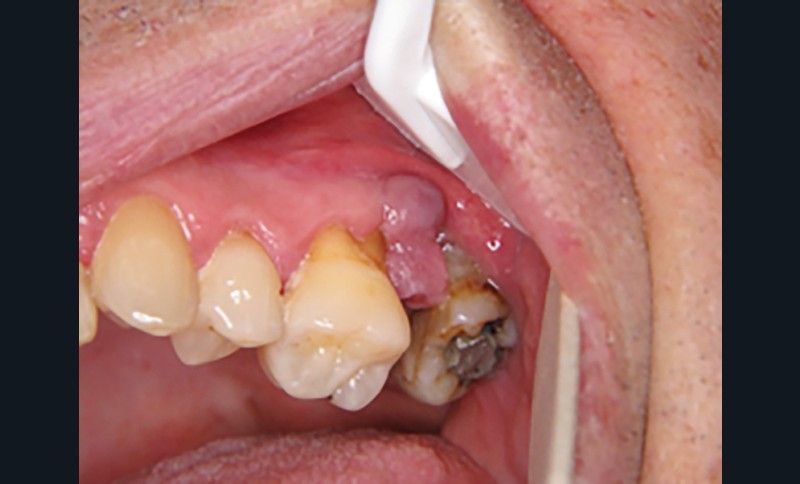

Motif de la consultation. Patient de 49 ans venu consulter pour une tuméfaction en distal de 26.

Histoire de la maladie. La lésion était présente depuis 8 mois sans tendance spontanée vers la régression.

Interrogatoire. Il ne mettait pas en évidence…